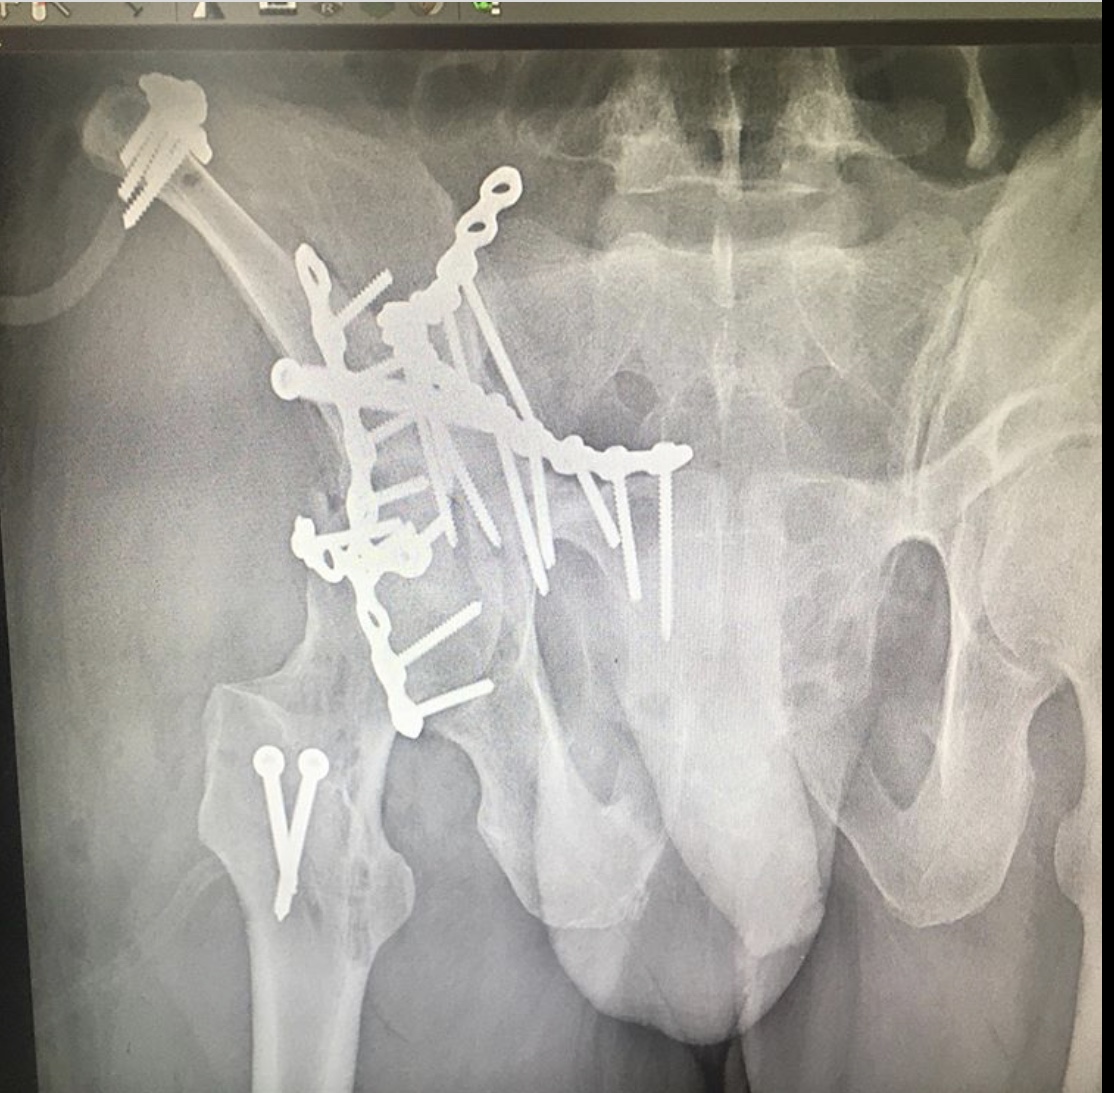

Как рассказал хирург – травматолог – ортопед ГКБ 7 Казани Руслан Ильгизарович Закиров, после стабилизации гемодинамических показателей был выполнен остеосинтез реконструктивными пластинами и винтами. При такой травме вероятность «выживания» тазобедренного сустава очень невелика. Но при любом развитии ситуации созданы условия для дальнейшего лечения и реабилитации пациента.